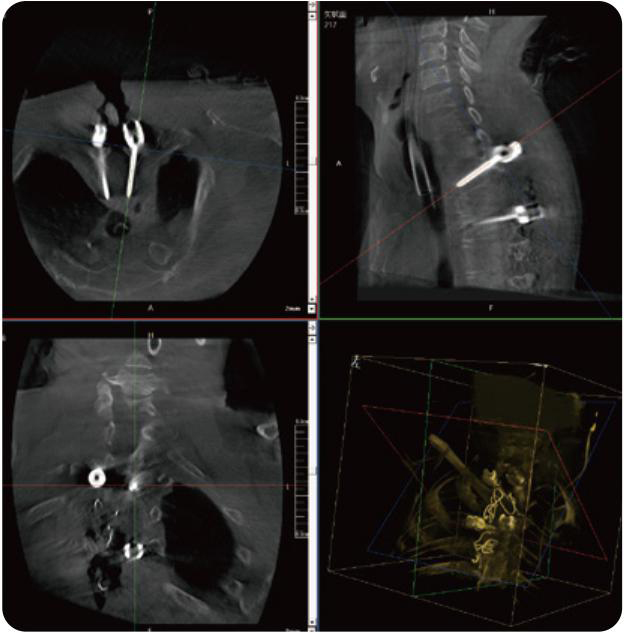

PL300B可应用于多节段脊柱外科手术,辅助医生定位病灶部位,为脊柱外科手术(经皮椎体成形术、椎弓根螺钉内固定术等术式)提供术前手术流程规划、入钉位置、角度可视化引导,模拟仿真入钉辅助。

PL300B搭配糖心vlog 自主研发生产的平板3D C形臂,借助一体化自适应配准( 轨迹配准)技术,通过追踪C形臂三维采集轨迹,自动完成图像坐标建立和系统坐标配准。配准精度更高,操作步骤少,系统运作效率高。